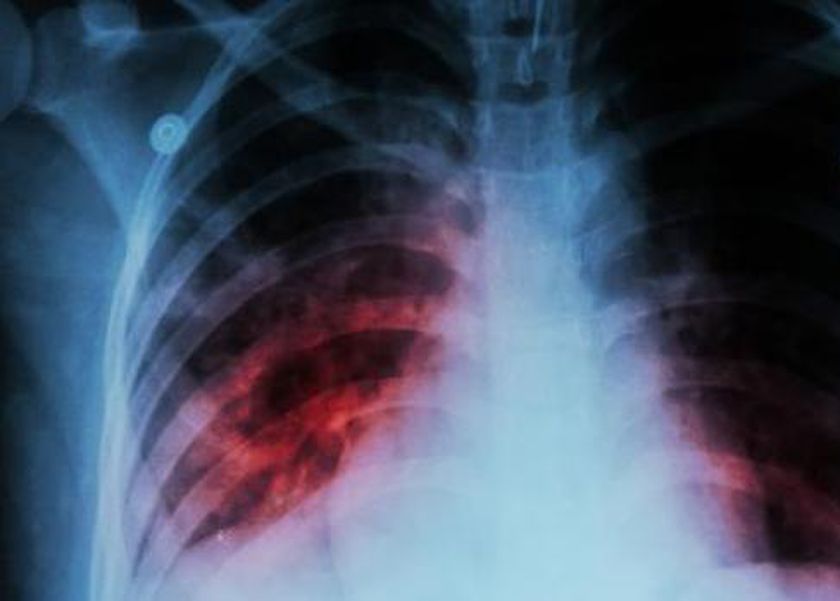

وكشفت أن الأعراض الرئيسية للدرن، تشمل السعال المستمر لأكثر من أسبوعين، فقدان الوزن غير المبرر، التعرق الليلي، والتعب المزمن، مشيرة إلى أن التشخيص يتم عبر اختبارات مثل فحص الجلد، تحليل البلغم، والتصوير بالأشعة السينية.